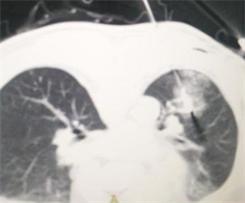

今日,我科再次为一肺部转移性肿瘤患者进行射频消融术。该患者为当地人,数年前确诊为颌面部恶性肿瘤,后经手术治愈。近日查胸部CT发现肺部有多发结节,经确诊,证实转移。在俞万钧副院长的指导下,我科顾霄,徐涛副主任医师成功对患者肺部转移性肿瘤进行定位,完整射频消融,接下去,将对患者消融的肿块进行随访,观察远期疗效。(徐涛)

图片2  瘤体完整被射频消融